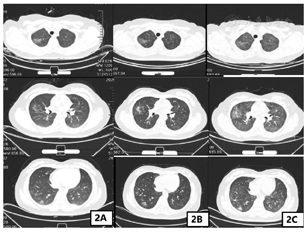

2019年12月5日—2020年2月13日行盆腔外照射(CTV 45 Gy/25 f,CTV 60 Gy/25 f)+阴道近距离放疗6 Gy×5 f,外照射放疗区域包括全子宫,全阴道,骨转移区,腹膜后、盆腔、腹股沟淋巴引流区,放疗期间行同步顺铂50 mg化疗6次。患者放疗及同步化疗结束后阴道穹窿及阴道前壁上1/3仍有残留病灶,建议患者补充全身静脉化疗,患者因自身对生活治疗要求高,坚决拒绝化疗。患者病理检测提示PD-L1阳性(CPS≥1),根据2020年NCCN指南及国内外临床试验PD-1抑制剂治疗推荐用于PD-L1表达阳性或MSI-H/d MMR表达的晚期宫颈癌的治疗,2020年3月13日—2020年9月1日行卡瑞丽珠单抗注射液200 mg,每2周1次,静脉滴注治疗,同时联合唑来磷酸抑制骨破坏。患者2020年7月30日使用卡瑞丽珠单抗10个疗程治疗后出现咳嗽,患者呼吸科就诊,口服止咳药及头孢抗炎治疗后咳嗽症状好转,无呼吸困难及气喘及气短症状,2020年8月14日完善胸部CT提示双肺多叶段新增多发斑片磨玻璃密度影,感染性病变?(图2A),结合患者病史及CT检查考虑为肺部感染可能性大,不除外免疫检查点抑制剂相关性肺炎,需密切监测患者症状及影像学检查。2020年8月16日行第11个疗程治疗后仍有咳嗽,但较前无明显加重,继续抗炎止咳治疗。2020年8月31日复查胸部CT提示双肺多叶段多发斑片磨玻璃密度影范围大致同前,部分密度较前增高,感染性病变?余胸部所见基本同前(图2B)。2020年9月1日行第12个疗程治疗,治疗后2 d患者出现气喘,进行性加重,治疗后7 d患者出现无明显自主咳嗽症状,刺激性气味可诱发咳嗽症状,不伴咳痰,静息状态下气喘尚可,体力活动后气喘加重,伴气短及呼吸困难,休息后可缓解,考虑患者为免疫检查点抑制剂相关性肺炎,遂急诊返院。2020年9月10日胸部CT提示双肺多叶、段模糊磨玻璃密度斑片影范围较前增多,请结合临床注意血管炎,药物性肺损伤?余胸部所见基本同前(图2C)。肺弥散功能提示肺总弥散量重度下降,单位弥散量轻度下降。肺通气功能提示重度混合性通气功能障碍,限制为主。免疫检查点抑制剂相关性肺炎美国国家综合癌症网(National Comprehensive Cancer Network,NCCN)指南[2]以临床结合影像学进行分级。具体标准:1级,无症状,病变局限于一叶肺或病变范围<25%的肺实质;2级,出现新的呼吸道症状或原有症状加重,包括气短、咳嗽、胸痛、发热,以及所需吸氧条件升高;3级,症状严重,病变累及所有肺叶或>50%肺实质,日常活动受限;4级,危及生命的呼吸损害。患者胸部CT提示双肺多叶、段模糊磨玻璃密度斑片影范围较前增多,病变累及部位>50%肺实质,结合患者症状诊断为免疫检查点抑制剂相关肺炎3级。